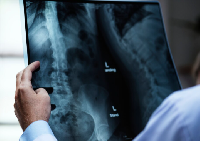

Выезд травматолога-ортопеда, рентгенолога Александра Валерьевича Дидковского.

На рабочем месте производится обучение работе на Вашем оборудовании.

Любого доктора можно быстро подготовить как рентгенлаборанта и дать необходимые знания для оценки рентгенограмм.

Изучение проблемы низкого качества рентгенограмм на Вашем оборудовании.